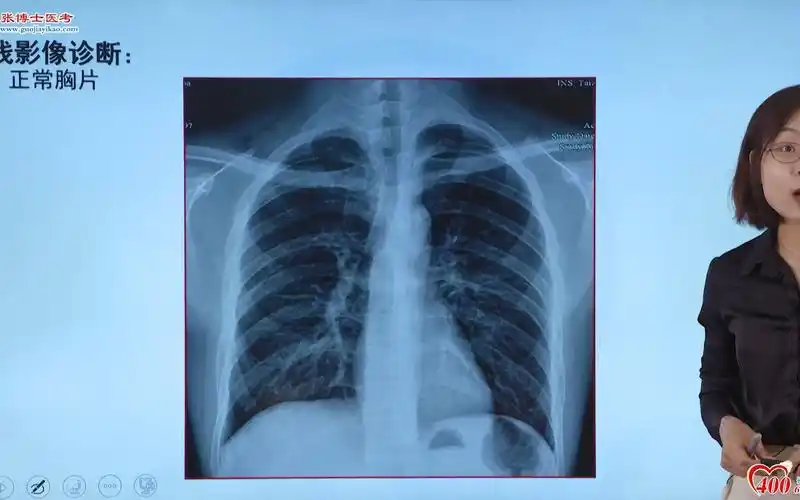

影像-正常胸片

影像解剖入门 | 正常胸片怎么看?